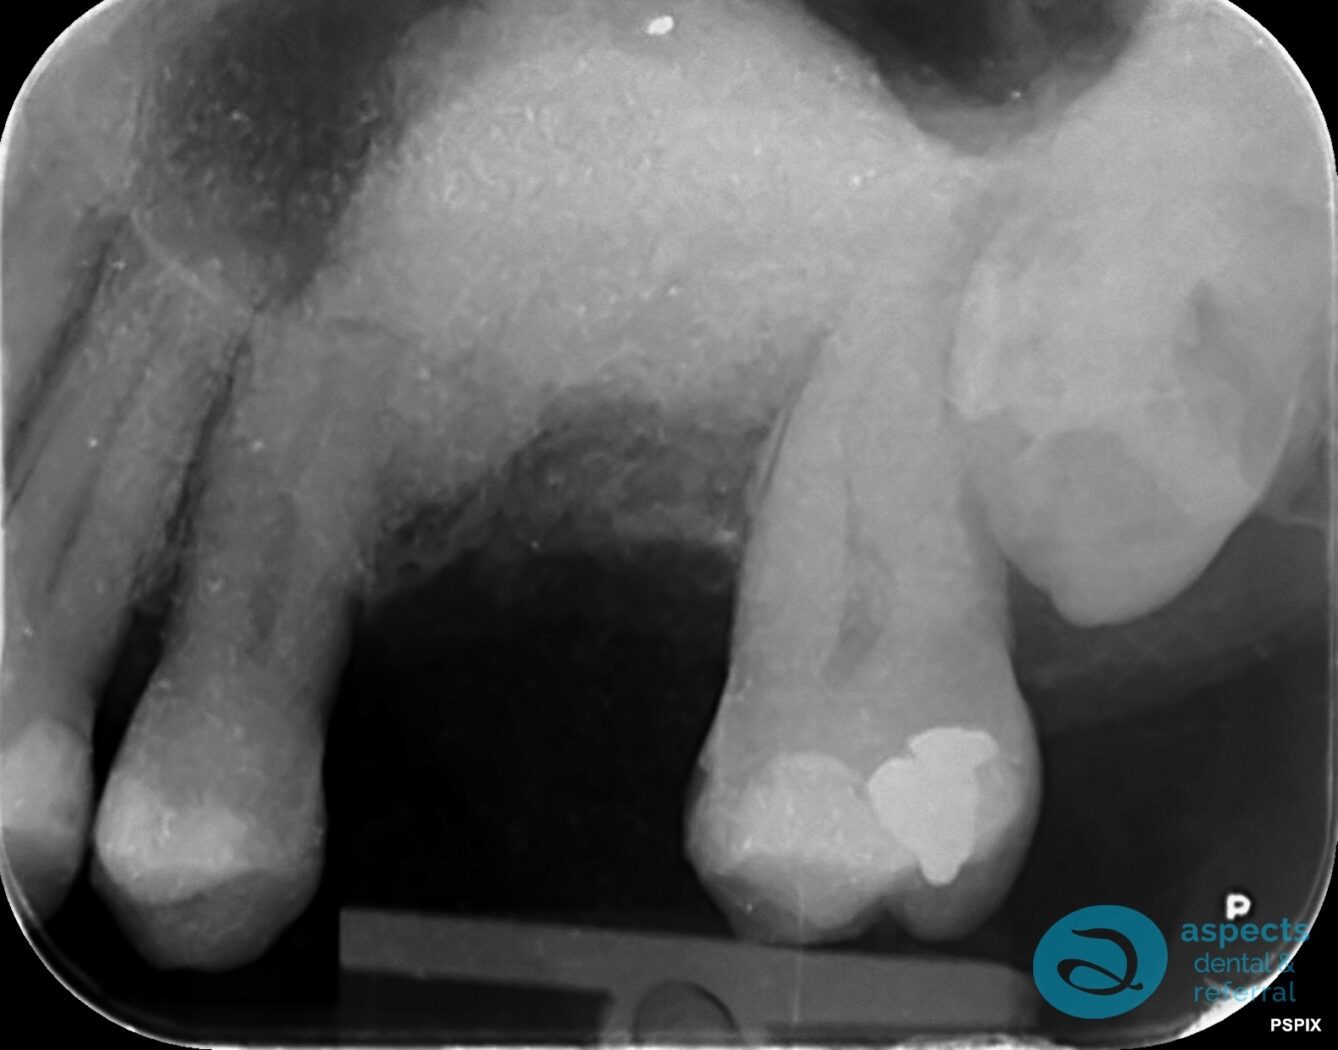

After Tooth Extraction & Sinus Lift Xray

Before Dental Implant & Bridge Xray

After Dental Implant & Bridge Xray